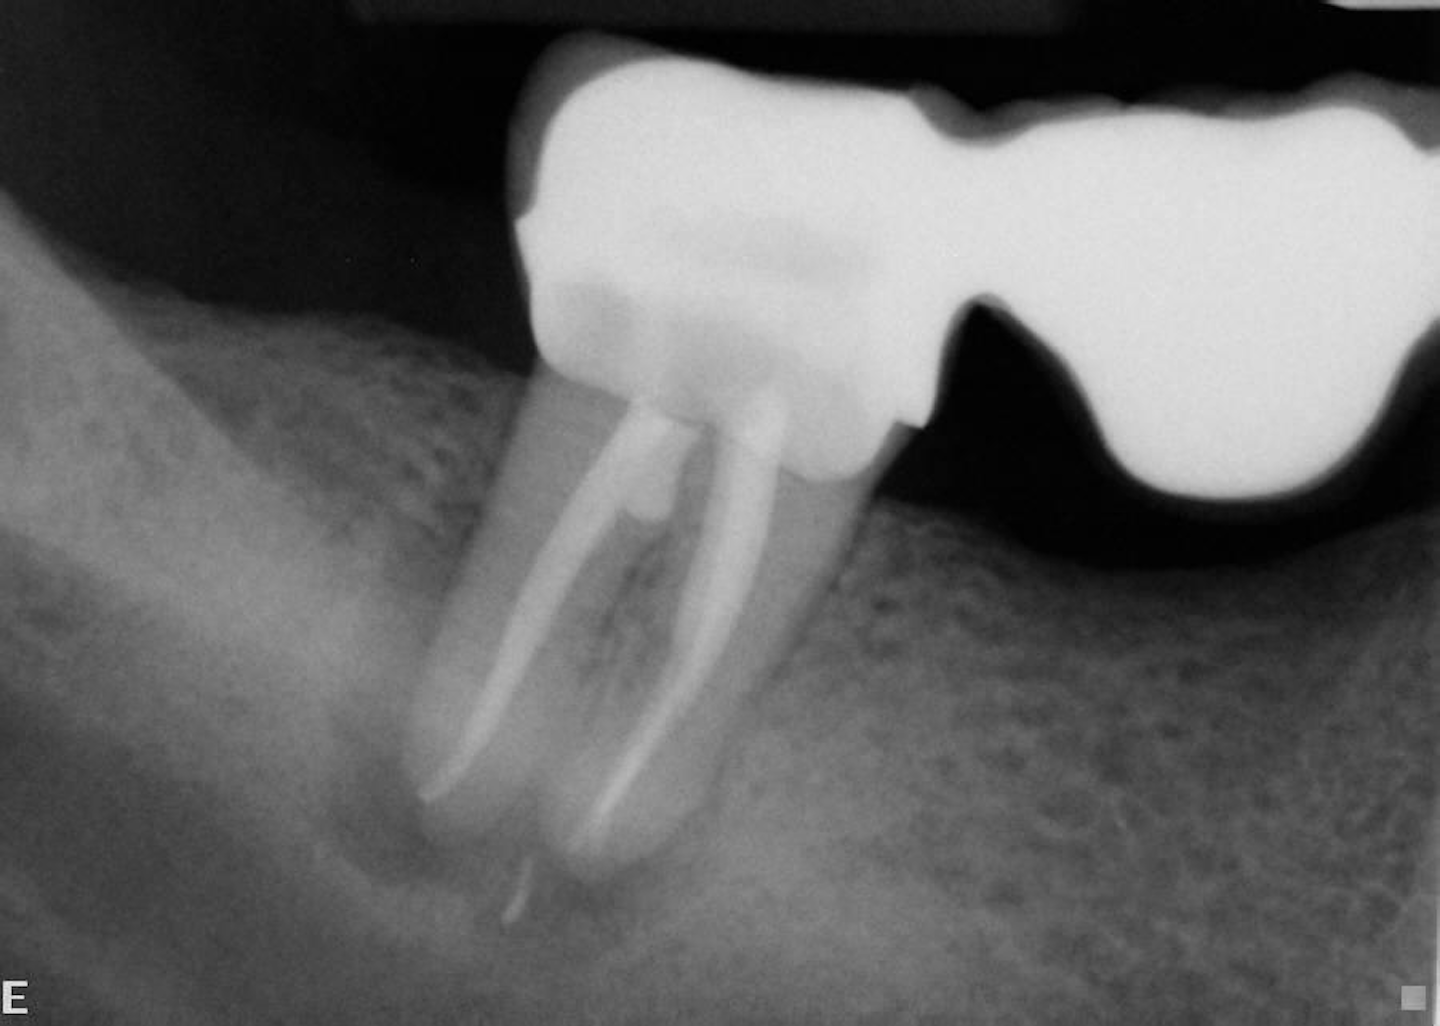

Primary endodontic lesion with secondary periodontal involvement. (a What Does Endodontic Lesion Mean Nonsurgical and surgical endodontic treatments have a high success rate in the treatment and. dentists are likely to encounter lesions that have both periodontal and endodontic aetiological components; What Does Endodontic Lesion Mean.